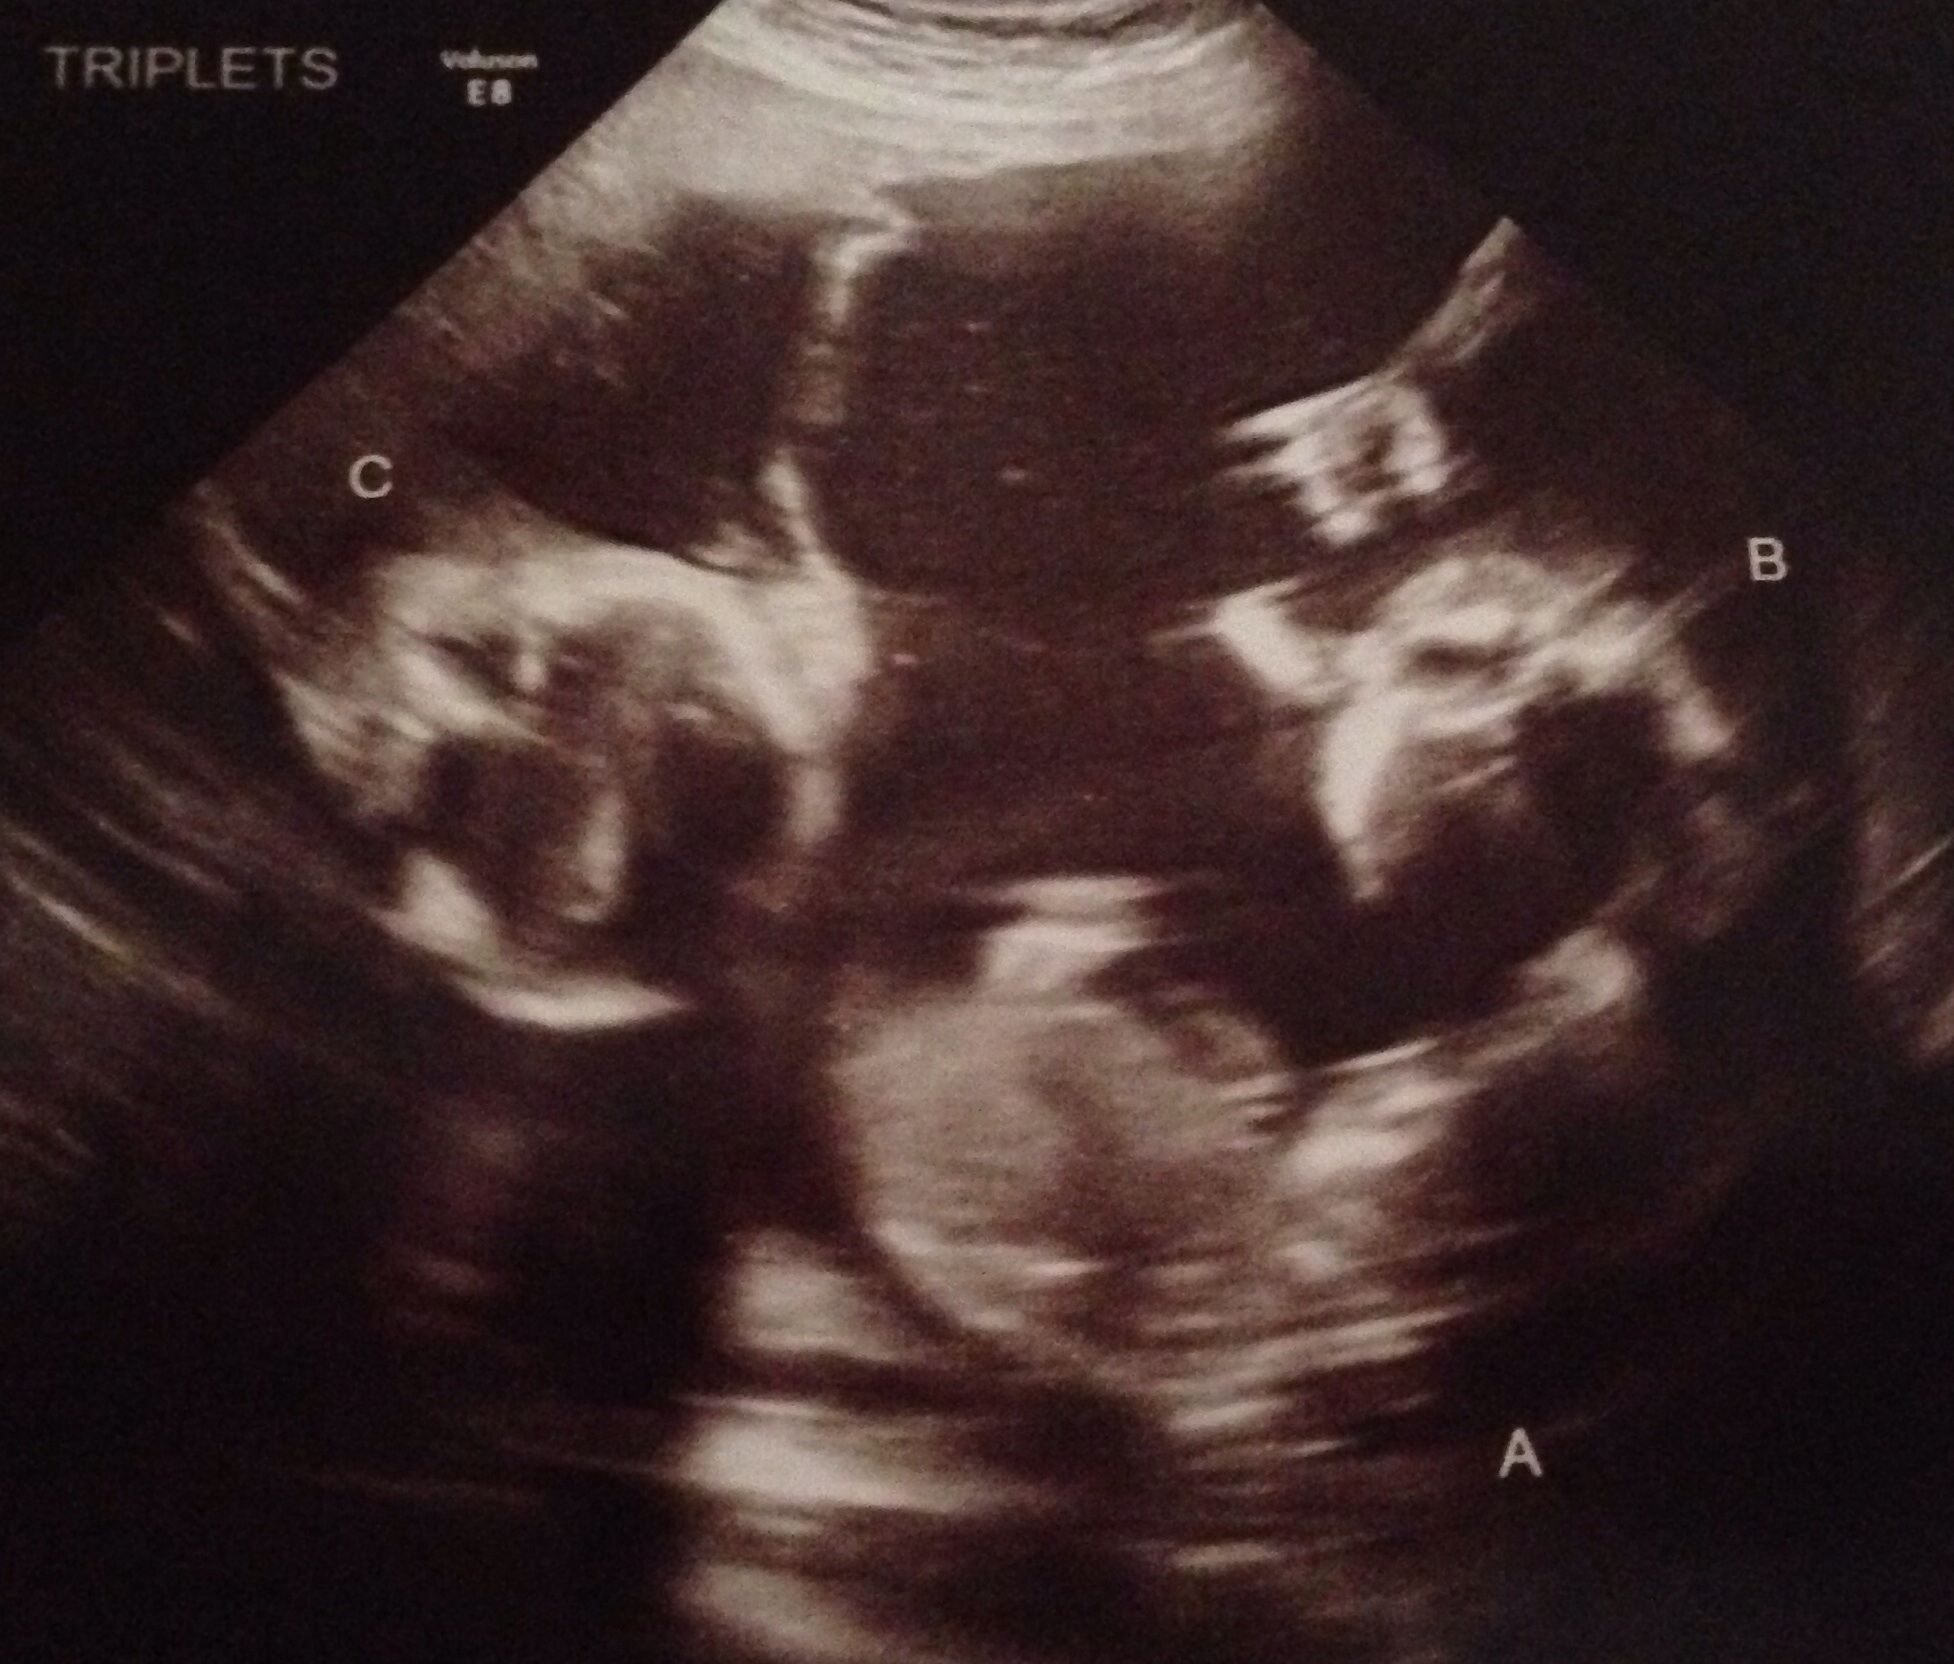

One of my favorite memories of the triplets was the moments we found out that our "identicals" we're girls and we were also having a boy! I will never forget Andy's face when the technician told us.

One other highlight would have to be when I started feeling them kick and move -especially the few times I could feel ALL THREE moving.

I very blessed to have these memories, even if there aren't as many as I had hoped.